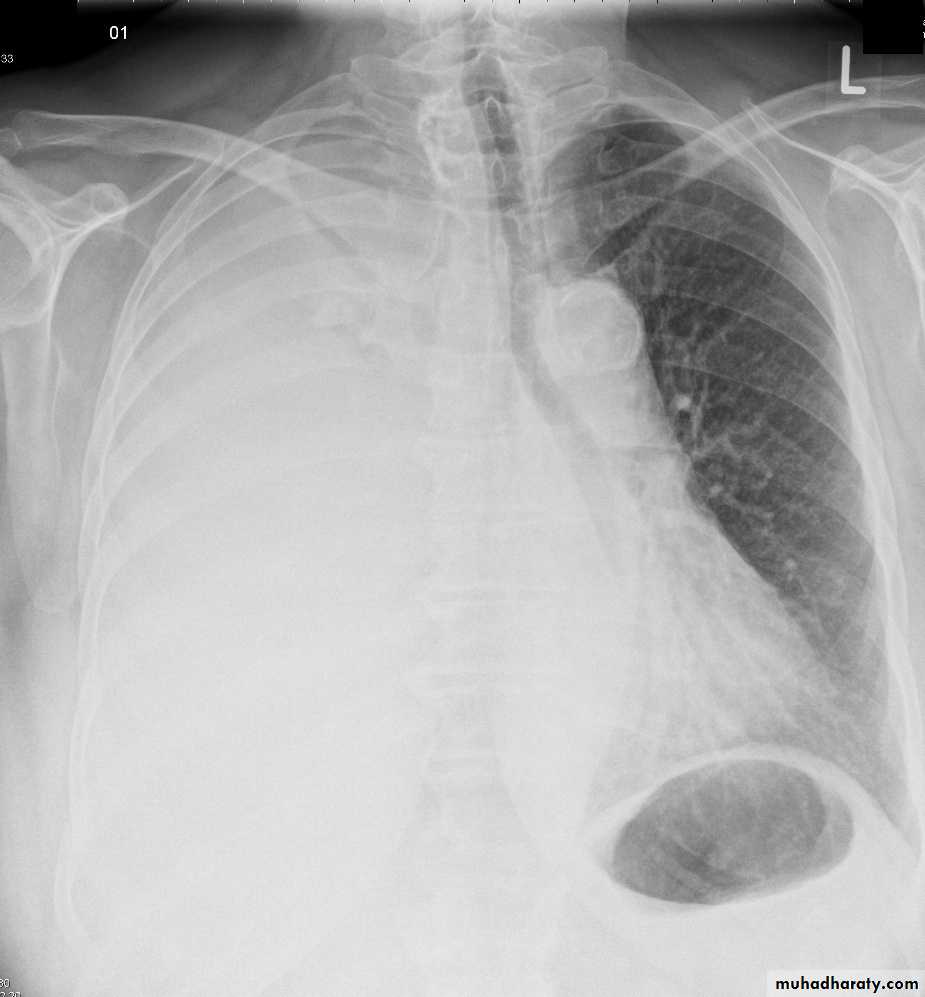

Homogenus opacity of the left hemithorax with shifting of the trachea to the same sidePleural effusion

Homogenus opacity of right lower zone with meniscus signOblitration of right cardiophrenic and costophrenic angles

Homogenus opacity of the right hemithorax

Oblitration of cardiophrenic and costophrenic angles

Shifting of the trachea to the opposite side

Pleural effusion

Homogenus opacity of right lower lobe with Oblitration of right cardiophrenic and costophrenic angles.

Meniscus sign

Encysted pleural effusionHomogenus opacity in the right lung with obtuse angle and obliteration of right costophrenic angle, normal cardiophrenic angleNote: this x ray has 2 ddx>>> empyema and encysted pleural effusion